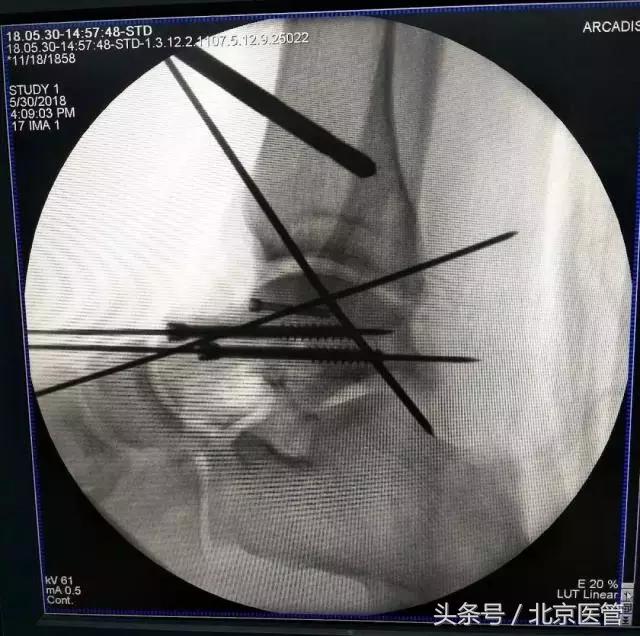

手术中

机器人为螺钉的置入提供精准的空间定位和稳定的路径,由于置入精度高,误差在1mm以下,在距骨形状复杂,螺钉通道狭长的情况下,实现了预定的内固定方案。